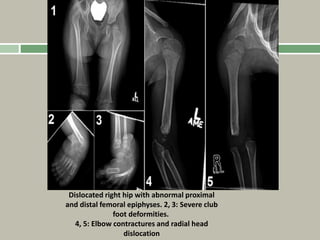

Diastrophic dysplasia

hitchhiker’s thumb,

though not classical. Note

the club feet.

Dislocated right hip with abnormal proximal

and distal femoral epiphyses. 2, 3: Severe club

foot deformities.

4, 5: Elbow contractures and radial head

dislocation